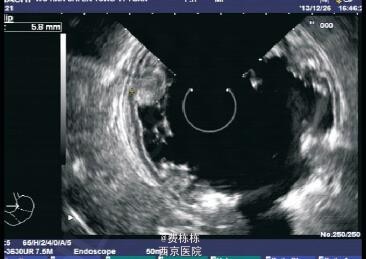

入院后给予抗感染(更昔洛韦、头孢美唑)、输注白蛋白(总量 1 g/kg,入院 1 周内分 3 次输注)及利尿等治疗,患儿水肿消退,腹痛及呕吐缓解 ,颈部淋巴结缩小,扁桃体分泌物消失。进一步行全身麻醉下电子胃镜及结肠镜检查,发现胃底及胃体黏膜明显充血水肿,呈结节样肥厚、隆起,其表面可见糜烂,质脆易出血,较多白色黏液覆盖黏膜表面;食管、贲门、胃窦、胃角、幽门、十二指肠球部未见异常。结肠镜检查未见异常。取胃窦及胃体黏膜活检,提示胃窦黏膜组织呈慢性炎症改变,嗜酸粒细胞约 1 个 /HPF;胃体黏膜上皮呈管状腺瘤样增生,固有膜及黏膜下层水肿明显,并见散在的炎性细胞浸润,嗜酸粒细胞最多约 15 个 /HPF,免疫组化检查示幽门螺杆菌(Hp)阴性,CMV 阴性。之后给予洛赛克抑酸、吉法酯保护胃黏膜等治疗。入院后第 16 天复查肝功能全套(9 项)TP 64.4 g/L,ALB 35.8 g/L,GLB 28.6 g/L,均较入院时升高,白蛋白仍低于正常值,电解质及血液分析未见异常。入院第 26 天在全麻下行超声胃镜检查,提示胃体可见多处的第二层无回声性增厚,最厚处达 5.8 mm,胃部周围未见明显增大的淋巴结。考虑诊断“蛋白丢失性胃病”(protein-losing gastropathy, - PLG)。